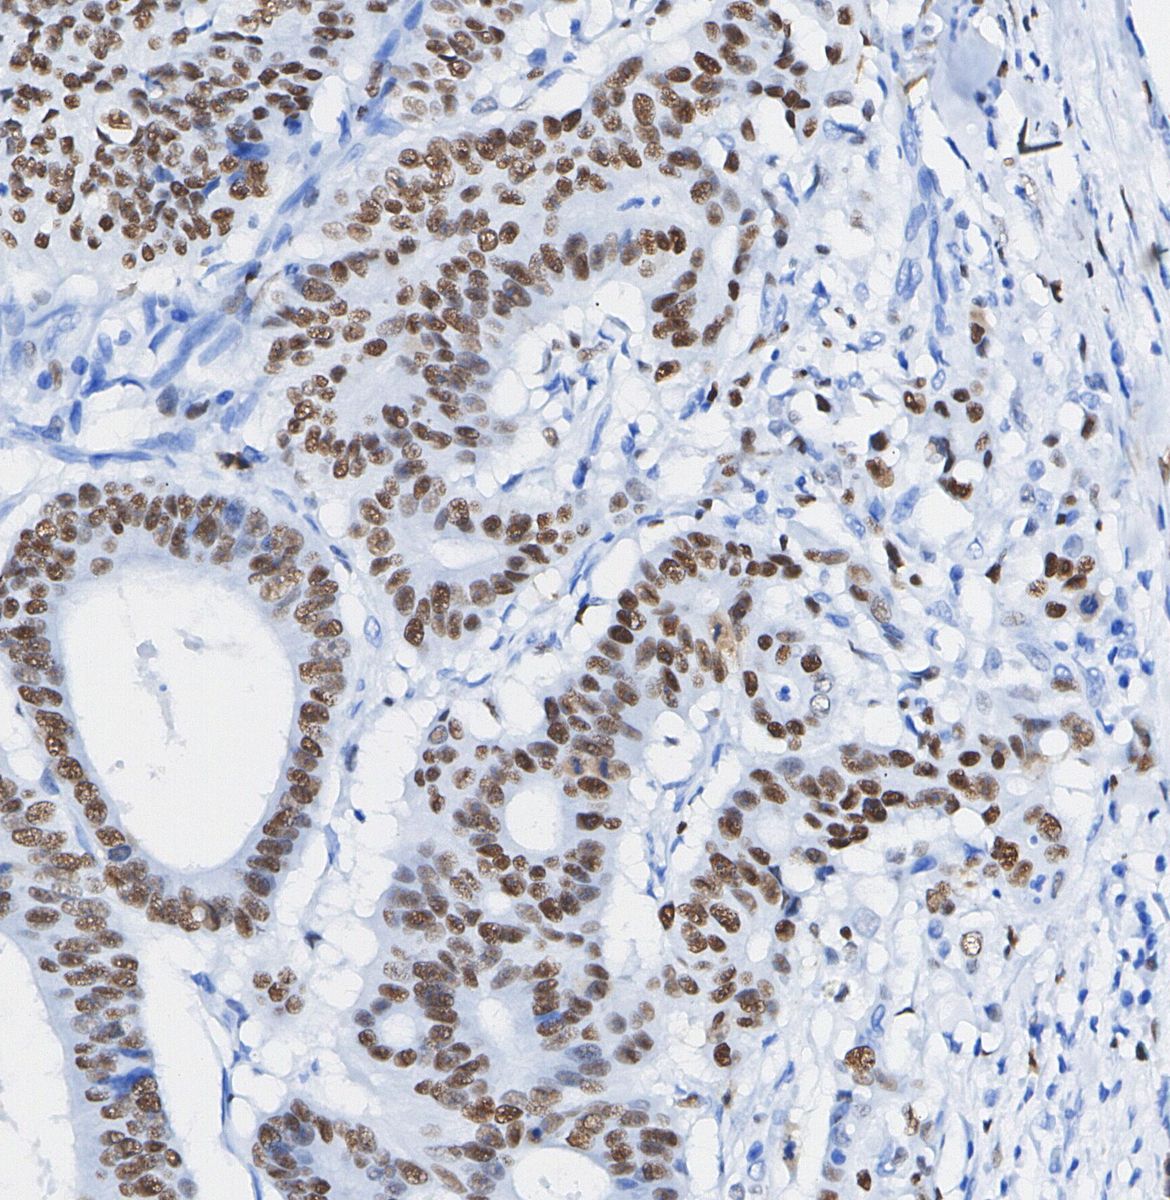

• Immunohistochemical analysis of formalin fixed paraffin embedded human Colorectal cancer tissue with F1321 at 1/100 dilution.